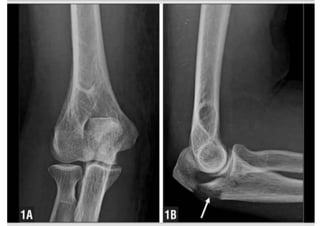

Radiographic Evaluation

• True lateral radiograph

Demonstrates:

• extent of the fracture

• degree of comminution

• degree of articular surface

involvement

• displacement of the radial head, if

present.

• AP view:

This shouid be evaluated to

exclude associated fractures or

dislocations.

The distal humerus may obscure

osseous details of the olecranon

fracture.